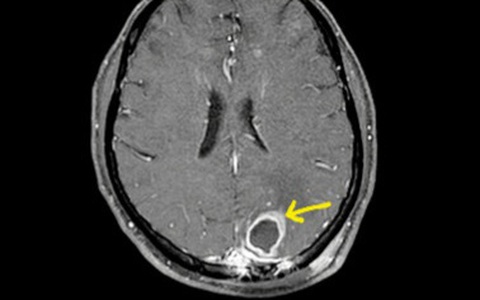

Thời gian qua, Bệnh viện Bạch Mai liên tục tiếp nhận nhiều bệnh nhân nhiễm vi khuẩn Whitmore (hay còn gọi là "vi khuẩn ăn thịt người"), trong đó có bệnh nhân phát hiện ổ áp xe trong não, mủ có chứa vi khuẩn Whitmore.